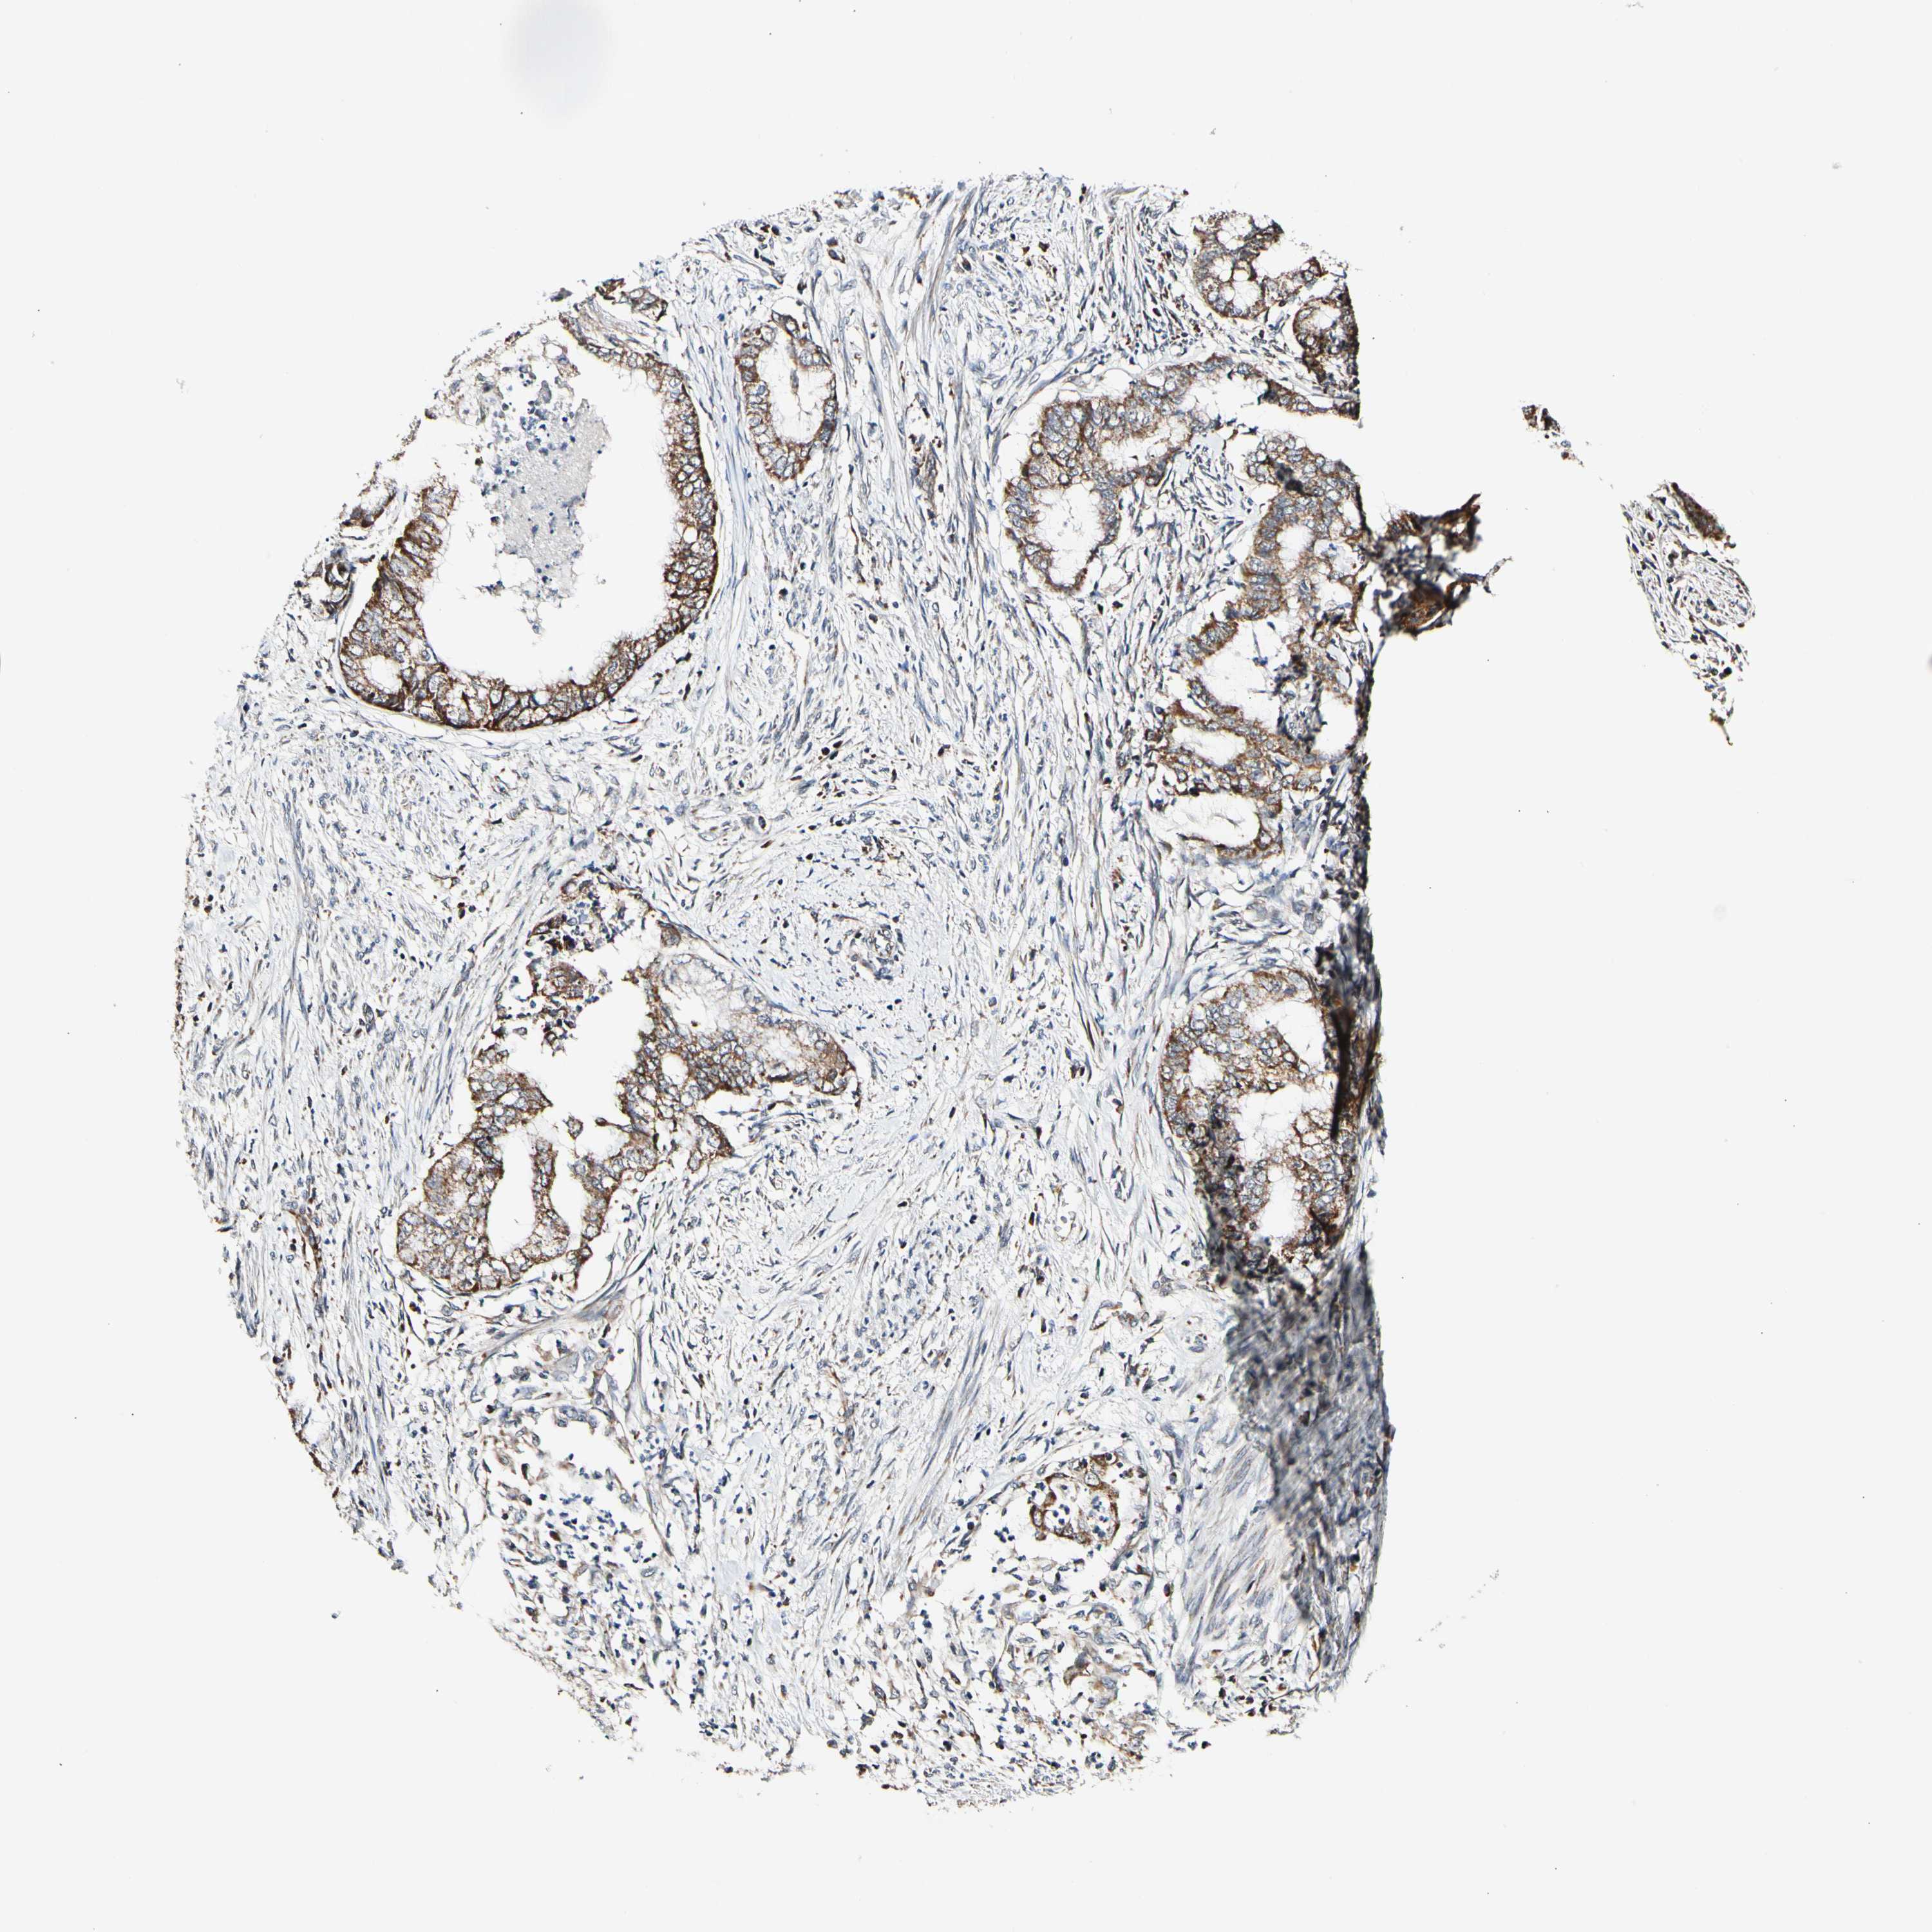

ENDOMETRIAL CANCER - Protein expressioni

A mouse-over function shows sample information and annotation data. Click on an image to view it in a full screen mode. Samples can be filtered based on level of antibody staining by selecting one or several of the following categories: high, medium, low and not detected. The assay and annotation is described here.

Note that samples used for immunohistochemistry by the Human Protein Atlas do not correspond to samples in the TCGA dataset.

Antibody stainingi

Antibody staining in the annotated cell types in the current human tissue is reported as not detected, low, medium, or high, based on conventional immunohistochemistry profiling in selected tissues. This score is based on the combination of the staining intensity and fraction of stained cells.

Each image is clickable and will lead to virtual microscopy that enables deeper exploration of all samples and also displays staining intensity scores, fraction scores and subcellular localization as well as patient and tissue information for each sample.

Antibody HPA008796

Staining

High

Medium

Low

Not detected

Intensity

Strong

Moderate

Weak

Negative

Quantity

>75%

75%-25%

<25%

None

Location

Nuclear

Cytoplasmic/membranous

Cytoplasmic/membranous,nuclear

Adenocarcinoma, NOS